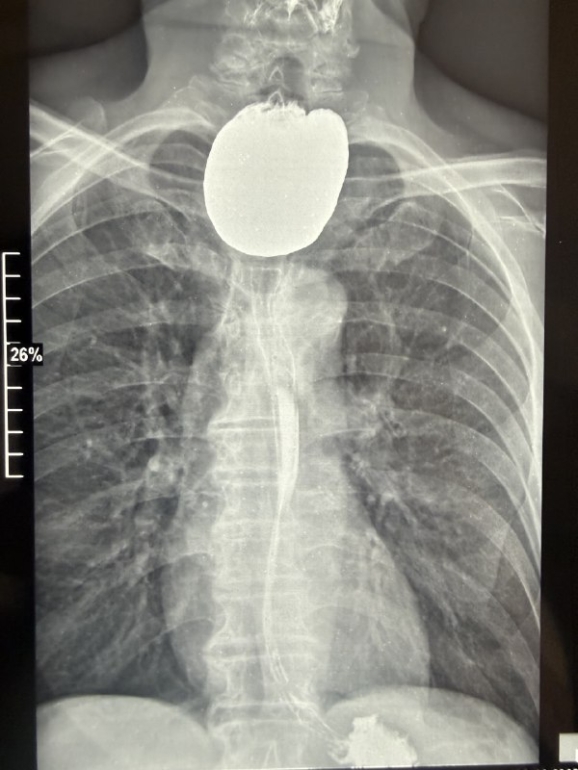

Мужчина поступил с жалобами на невозможность нормально питаться и постоянное срыгивание. Диагностика — рентгеноскопия и эзофагогастродуоденоскопия (ЭФГДС) — выявила образование размером 7 на 5 сантиметров, где скапливалась пища. Распространенность такой патологии не превышает 0,11%, а ее гигантские формы, требующие операции, встречаются в единичных случаях.